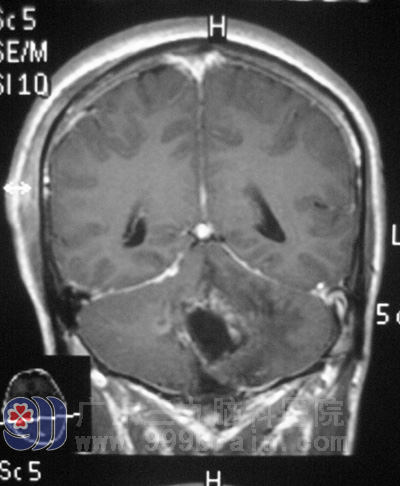

本来生活美好的一家人从此陷入了阴霾之中。阿辉的头痛一天比一天严重,呕吐越来越频繁,精神食欲也越来越差。为了得到更好的治疗,他们来到广东三九脑科医院综合神经外科求医。鲁明主任详细了解了阿辉的病情后,立刻组织专家团队制定周密的手术方案。阿辉入住广东三九脑科医院的第二天,就顺利接受了小脑半球肿瘤切除术。在术后精心治疗和护理下,阿辉慢慢地醒了,头也不痛不晕了,一家人总算是“守得云开见月明”。http://www.999brain.com/

手术后